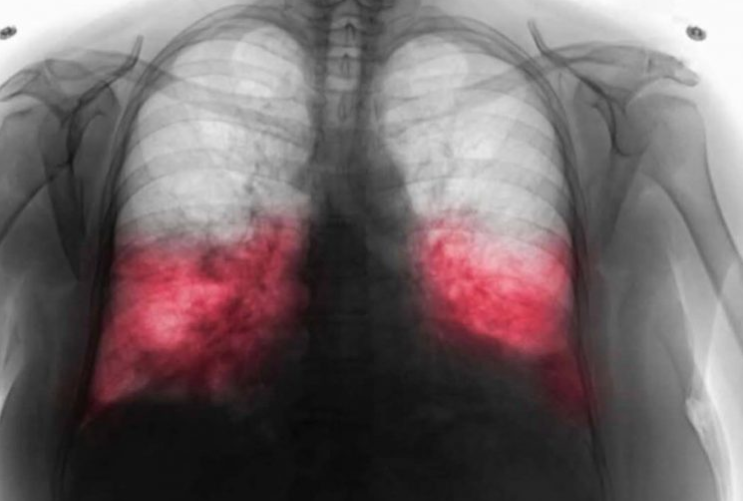

Ako postoji sumnja na hodajuću upalu pluća, doktor će obaviti detaljan pregled, uključujući laboratorijske testove i, ako je potrebno, rendgenski snimak pluća. U nekim slučajevima, doktor može uzeti briseve iz dišnih puteva kako bi se precizno odredio uzročnik. Hodajuća upala pluća obično zahtijeva specifične antibiotike koji ciljaju određene bakterije, jer obični antibiotici često nisu dovoljno učinkoviti.